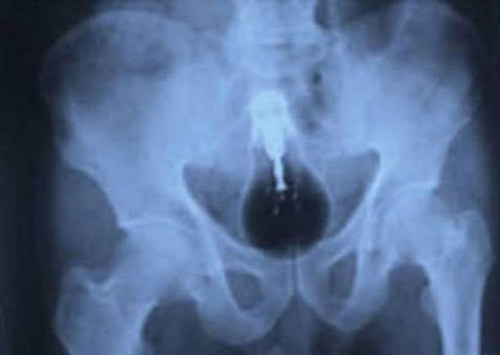

Hình ảnh X – quang này thuộc về một người đàn ông sống tại Trung Quốc. Cảm giác đau đớn vùng bụng khiến anh buộc phải tìm đến sự giúp đỡ của bác sĩ. Anh nói không biết lí do vì sao lại cảm thấy như vậy. Chỉ đến khi tiến hành chụp X – quang phát hiện dị vật mắc kẹt trong cơ thể, anh mới thừa nhận chính mình nhét nó vào và không thể tự lấy ra được.

Trong lúc “tự sướng”, người đàn ông này vô tình để chiếc máy rung đi sâu vào cơ thể. Dù vậy thay vì đến các cơ sở y tế gần nhất để lấy dị vật, anh ta lại cố gắng tự lấy máy rung bằng một chiếc kẹp salad khiến nó cũng nằm lại trong đó.